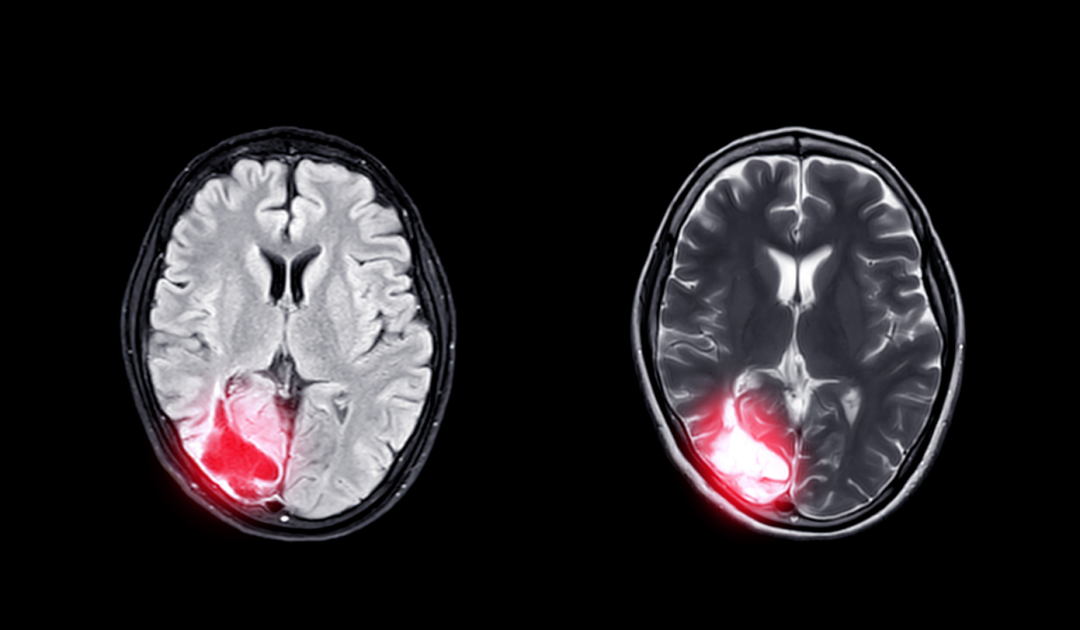

大脑作为人体的“司令官”,必须保证充足的血液供应才能够完成一系列生命活动,供血不足若不及时治疗,很可能引起痴呆、突然晕厥,甚至猝死、脑梗死等现象,必须给予足够的重视。

如果出现头晕头痛、失眠多梦、耳鸣、记忆力明显减退、肢体麻木等症状,且持续2个月以上,应及时就医进行脑电图、脑CT血管造影、核磁共振血管造影、经颅多普勒超声等相关检查,以便确诊。